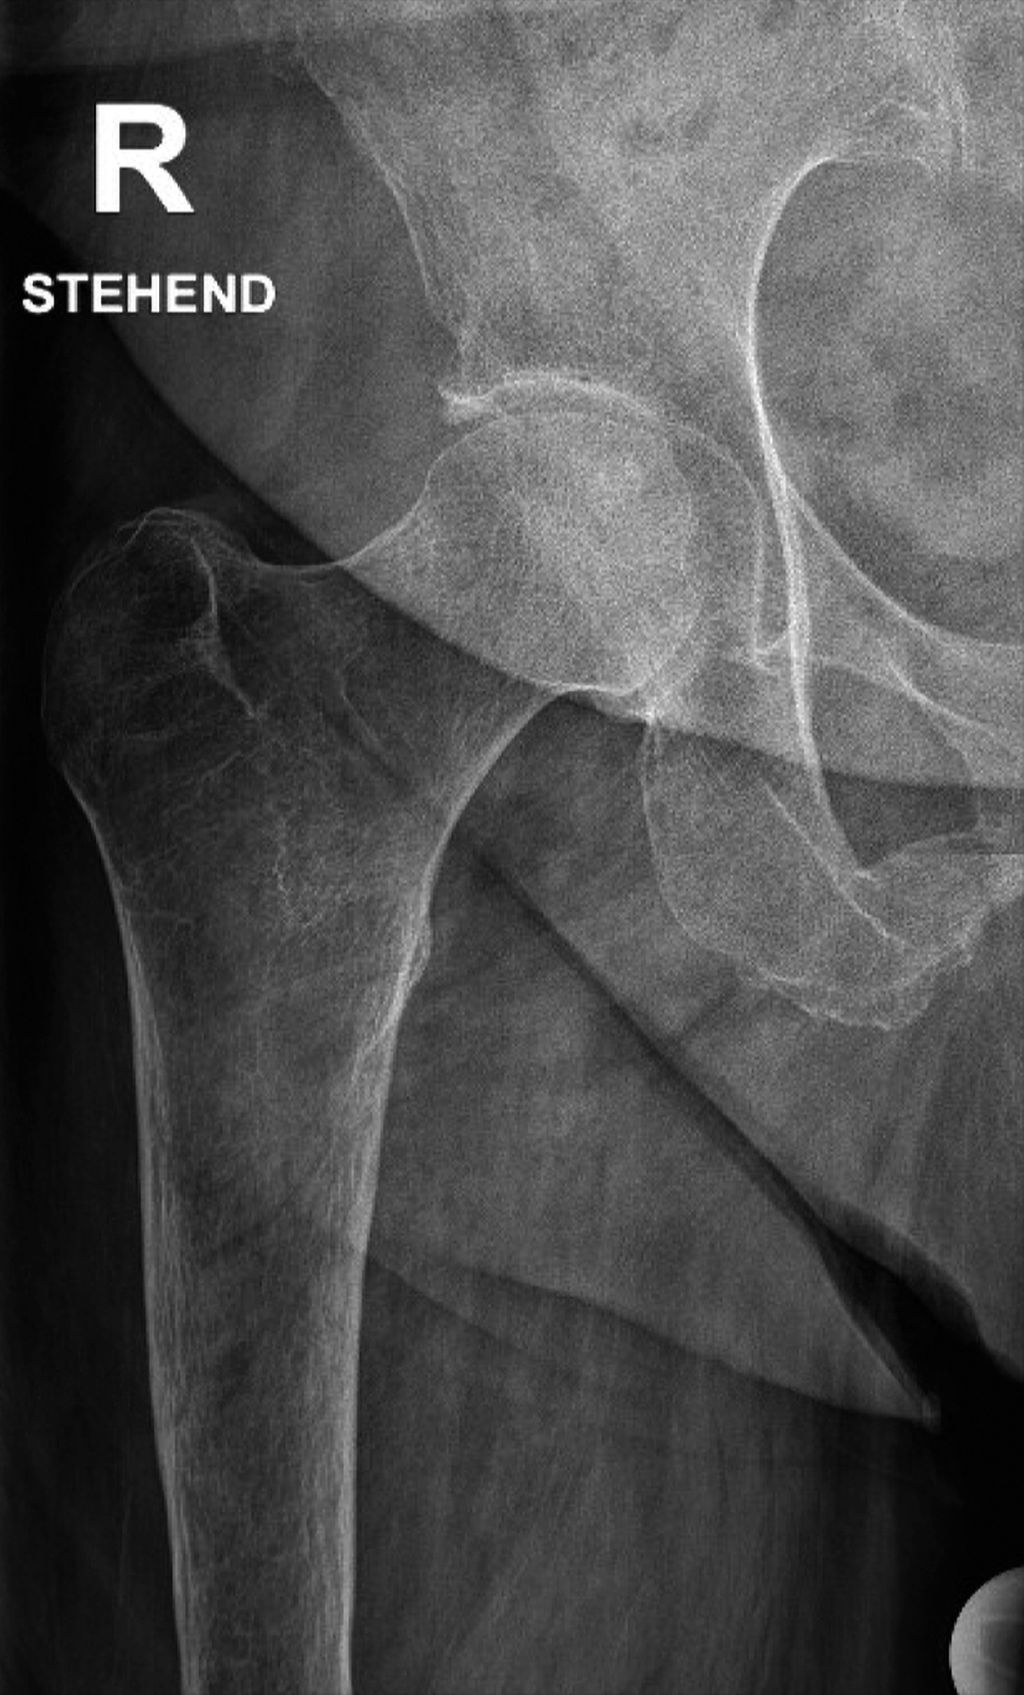

Abb. 1: Ein weibliches Dorr-C-Femur mit einer sehr dünnen Kortikalis und einem breiten Markraum. Bei einer solchen Femurkonfiguration zeigte eine zementierte Femurkomponente ein geringeres Risiko einer aseptischen Lockerung oder Fraktur im Vergleich zu einer zementfreien Variante. Das abgebildete Femur zeigt einen niedrigen Cortical Index, einen niedrigen Canal Flare Index, eine höhere Canal Calcar Ratio und eine höhere Canal Bone Ratio. Diese Werte sind alle mit osteoporotischen Veränderungen im Bereich des Femurs assoziiert

Auch die Ursache der Arthrose, die zur endoprothetischen Versorgung führt, spielt eine Rolle im Risikoprofil. So haben Rheumatiker:innen, aber auch Patient:innen, die eine vorangegangene Fraktur hatten, ein erhöhtes Risiko für PPF.3,15 Die Kombination aus weiblichem Geschlecht, einem Dorr-C-Femur und schlechter Knochenqualität sowie einem geriatrischen Patienten mit Sturz- und Stolperneigung hat das höchste Risiko einer PPF (Abb. 1).